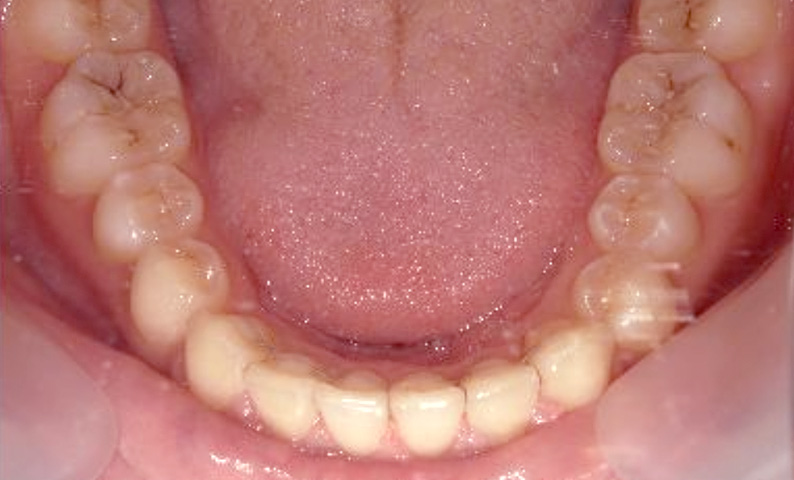

症例_002 下顎だけの部分矯正

治療期間:4ヶ月金額:30万円+税女性前歯のガタガタ下の前歯だけ

| Before | After |

|---|---|

|